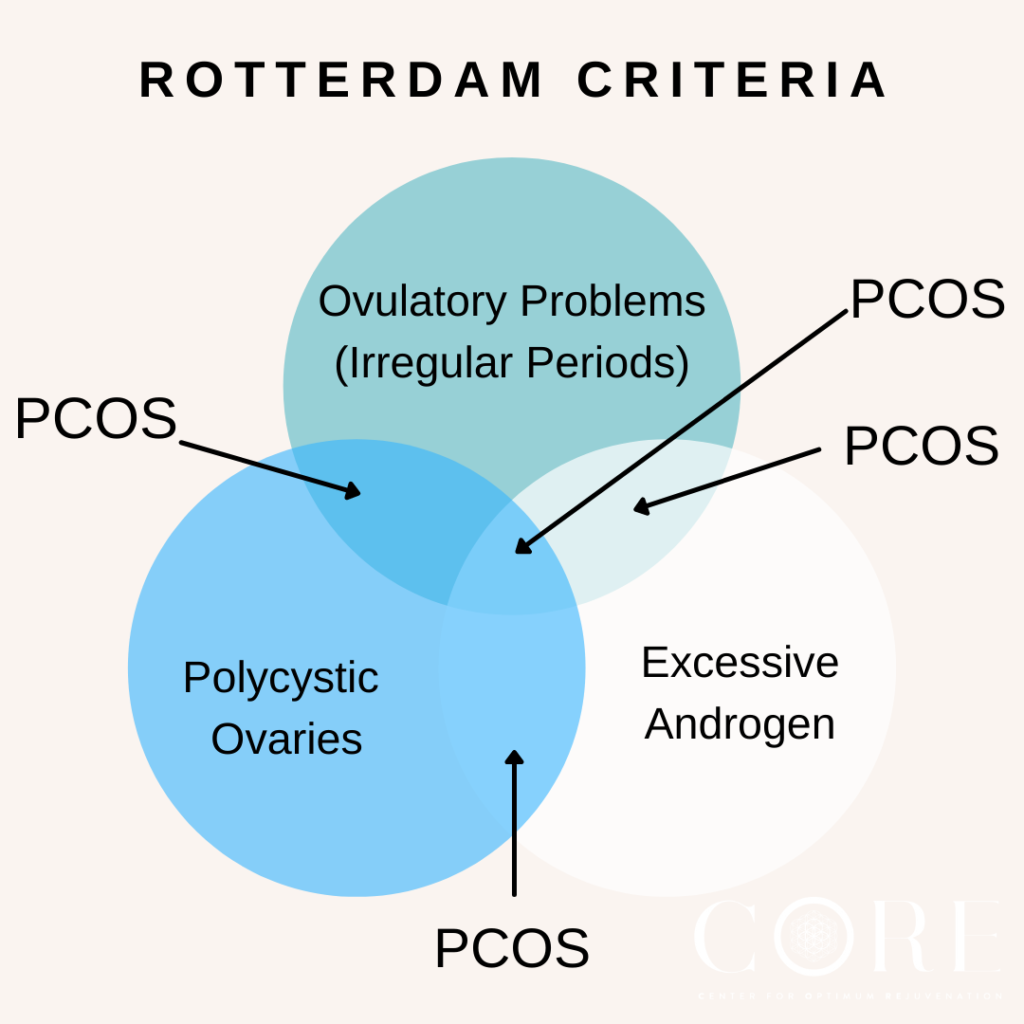

1. The Gold Standard: The Rotterdam Criteria

Most gynaecologists, including our Obstetrics and Gynaecology specialists at Island Hospital, rely on the Rotterdam Consensus Criteria for diagnosis. To be diagnosed with PCOS, a woman must exhibit at least two out of the following three criteria:

- Irregular or Absent Periods (Oligo- or Anovulation)

Indicating that ovulation occurs infrequently or not at all. - Signs of High Androgen Levels (Hyperandrogenism)

This can be evident through clinical signs (hirsutism, acne, male-pattern baldness) or confirmed via blood tests. - Polycystic Ovaries on Ultrasound

Showing 12 or more small follicles (2–9 mm in diameter) in one or both ovaries, and/or an increased ovarian volume.

How does a gynecologist diagnose PCOS?

A gynecologist diagnoses PCOS using the Rotterdam Criteria, requiring at least two out of three findings: irregular or absent periods, signs of high androgen levels (blood tests or clinical symptoms like hirsutism), and/or polycystic ovaries visible on a pelvic ultrasound.

This is an exclusionary diagnosis, meaning other conditions with similar symptoms (like thyroid issues or high prolactin) must first be ruled out.